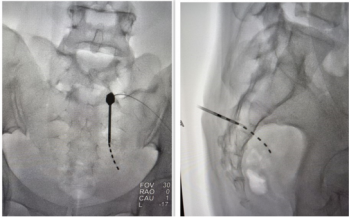

神经外科二病区介入团队、科主任姚声涛、副主任范瑞明、夏湘平副主任医师、张福安主治医师火速集结,严阵以待。患者被迅速送入介入手术室,一场“大脑保卫战”紧张展开。手术过程高效顺利,从穿刺开始至成功取出堵塞血管的血栓,实现血管再通,总计耗时不足15分钟!术后造影显示,原先闭塞的血管血流恢复通畅,显影良好。更令人欣慰的是,患者术后神志很快转清,能够正常交流,右侧瘫痪肢体的肌力也基本恢复正常。

左侧大脑中动脉开通通畅,显影良好

此次救治成功的关键在于“快”。从患者发病到血管成功再通,总时长控制在2小时的“黄金救治窗”内。尤其是取栓手术环节的迅速完成,最大程度降低了脑组织缺血坏死的风险,为患者良好的预后奠定了坚实基础。这不仅得益于患者家属的及时送医,更凸显了医院卒中团队流畅的协作流程、精准的决策能力以及介入团队娴熟的技术水平。